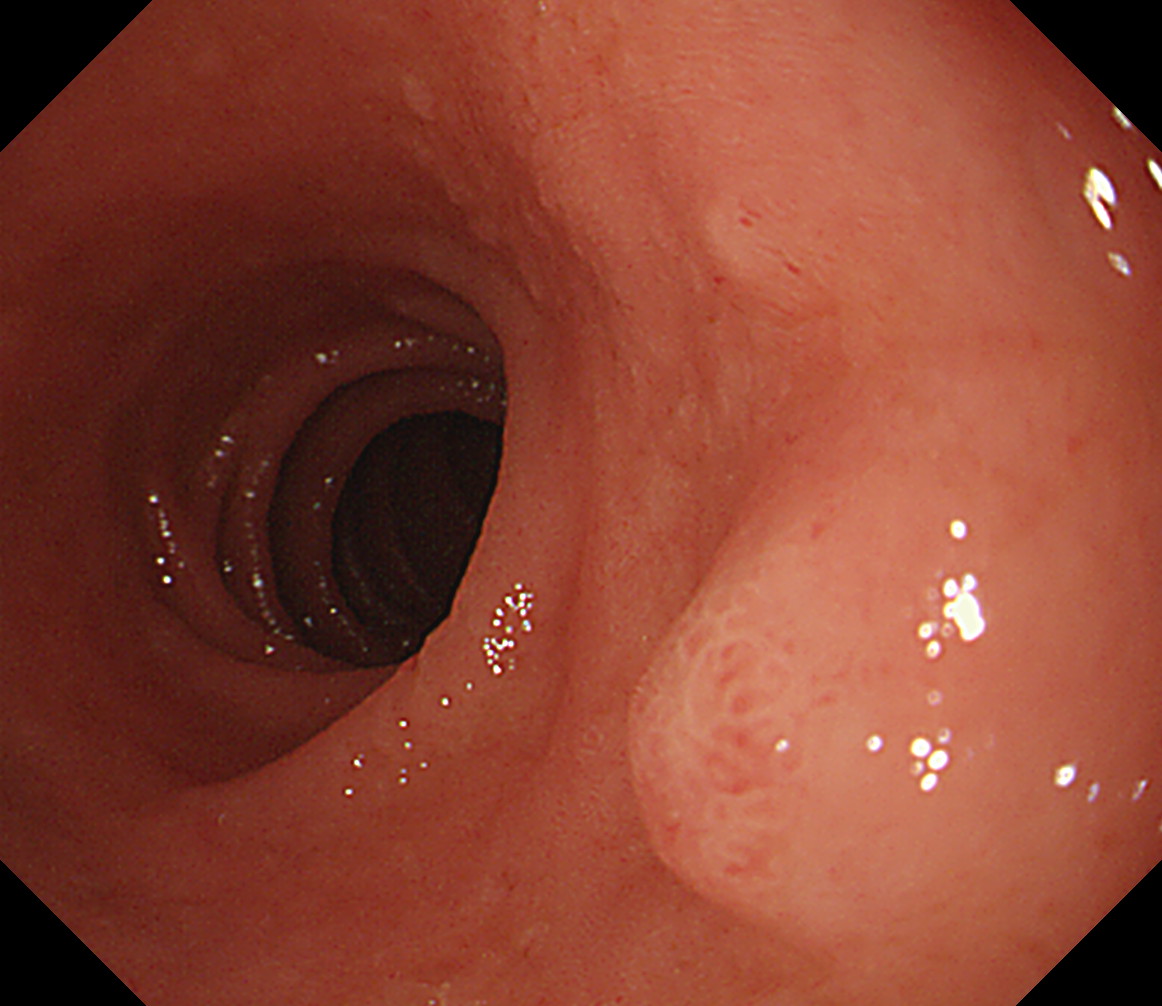

8 幽門輪 いわゆる「PーRing」 幽門輪

9 十二指腸球部前壁 十二指腸球部前壁

10 十二指腸球部後壁 この後十二指腸下降脚とVater乳頭を観察します 中部食道